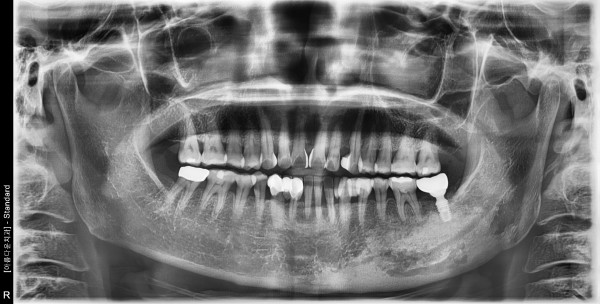

57세여자환자 / 하악좌측구치부발치후 뼈이식및 임플란트식립